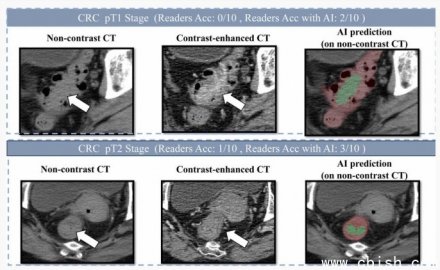

肠癌筛查迎来新突破:达摩院AI模型让无创筛查更准、更轻松 近日,阿里巴巴达摩院联合广东省人民医院等多家医疗机构,正式发布一款专为肠癌筛查设计的AI辅助诊断模型——DAMO CO...